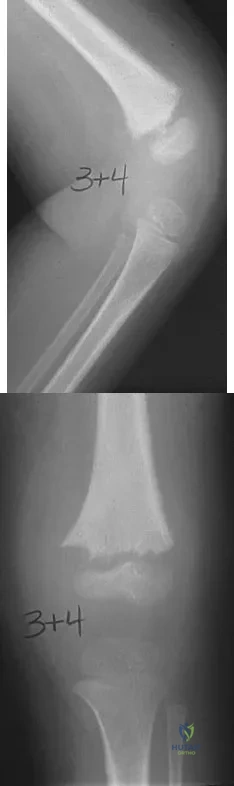

Which of the following choices best describes the fracture pattern shown in Figures 2a through 2c?

Explanation